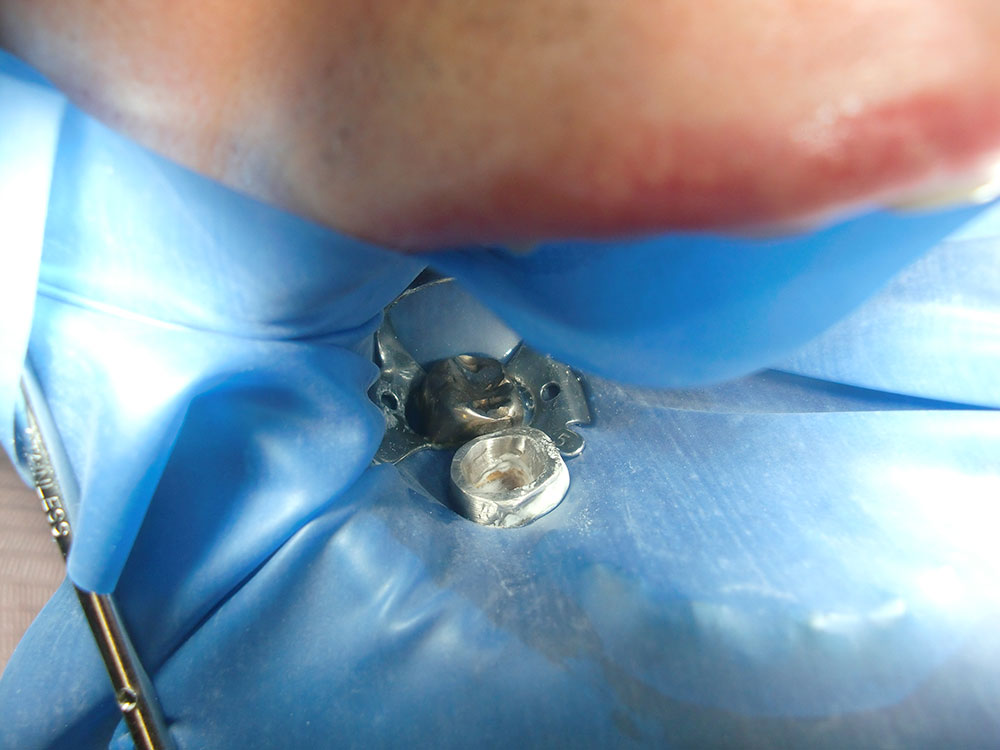

そのため当クリニックではやり直しの治療を少なくするため、ラバーダムというゴムのシートを全例にかけて、無菌的に処置します。

ラバーダムとは

次の写真のようにゴムのシートをかけ、治療する歯だけを出し、その歯と周りを消毒してから治療を始めます。

このゴムのシートをかけると、なんとやり直しの治療を85%も防ぐことができるんですよ。